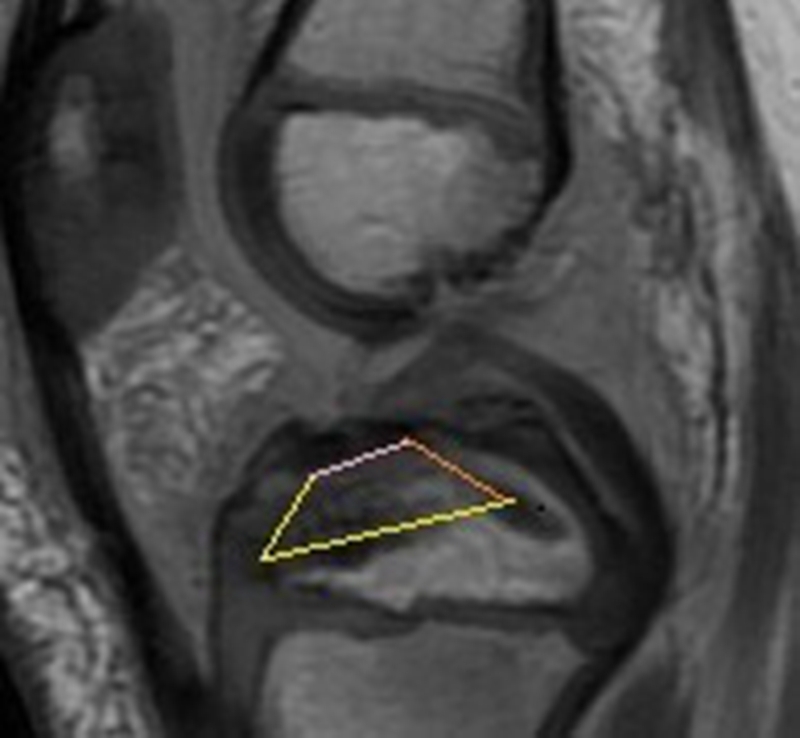

术前在显示前叉韧带全长的MRI矢状位上,按照预置内、外排锚钉之直径、长度和击入方向,规划生长板上内固定物所占空间尺度,如图8所示。内排钉选择直径3.0mm,长度10.8mm可吸收锚钉,内置双色半可吸收2号骨科高强缝线(Gryphon BR);外排钉选择直径4.75mm,长度17.8mm可吸收锚钉(Healix Advance BR Knotless)。

图8 术前MRI上规划胫骨生长板上内、外排锚钉置入之空间尺度